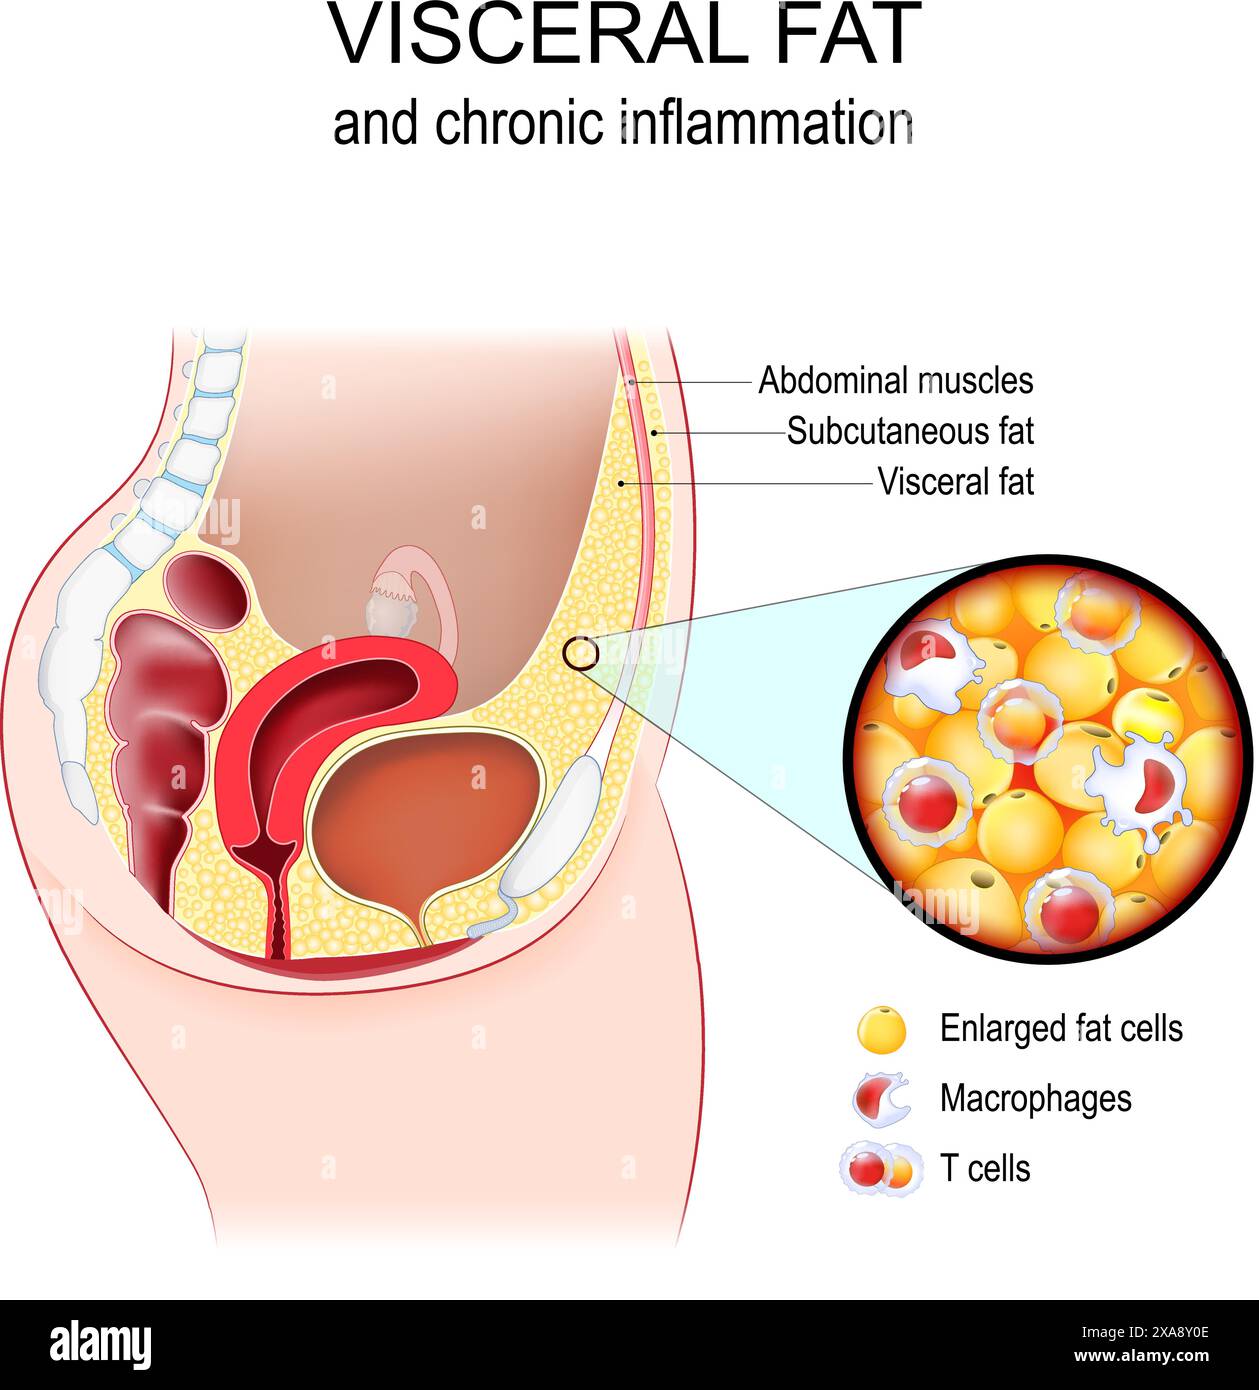

Graisse viscérale et inflammation chronique. Coupe transversale de l'abdomen féminin avec muscle abdominal, graisse sous-cutanée et viscérale. Gros plan de tiss adipeux Illustration de Vecteurhttps://www.alamyimages.fr/image-license-details/?v=1https://www.alamyimages.fr/graisse-viscerale-et-inflammation-chronique-coupe-transversale-de-l-abdomen-feminin-avec-muscle-abdominal-graisse-sous-cutanee-et-viscerale-gros-plan-de-tiss-adipeux-image608706238.html

Graisse viscérale et inflammation chronique. Coupe transversale de l'abdomen féminin avec muscle abdominal, graisse sous-cutanée et viscérale. Gros plan de tiss adipeux Illustration de Vecteurhttps://www.alamyimages.fr/image-license-details/?v=1https://www.alamyimages.fr/graisse-viscerale-et-inflammation-chronique-coupe-transversale-de-l-abdomen-feminin-avec-muscle-abdominal-graisse-sous-cutanee-et-viscerale-gros-plan-de-tiss-adipeux-image608706238.htmlRF2XA8Y0E–Graisse viscérale et inflammation chronique. Coupe transversale de l'abdomen féminin avec muscle abdominal, graisse sous-cutanée et viscérale. Gros plan de tiss adipeux